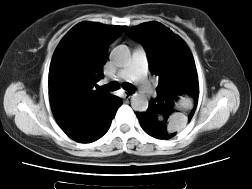

问题 女,52岁,左侧背痛1月,胸部CT如图,最可能的诊断为 ( )

选项 A.左肺中央型肺癌 B.左肺周围型肺癌 C.左肺感染 D.左肺炎性假瘤 E.肺隔离征

答案 D